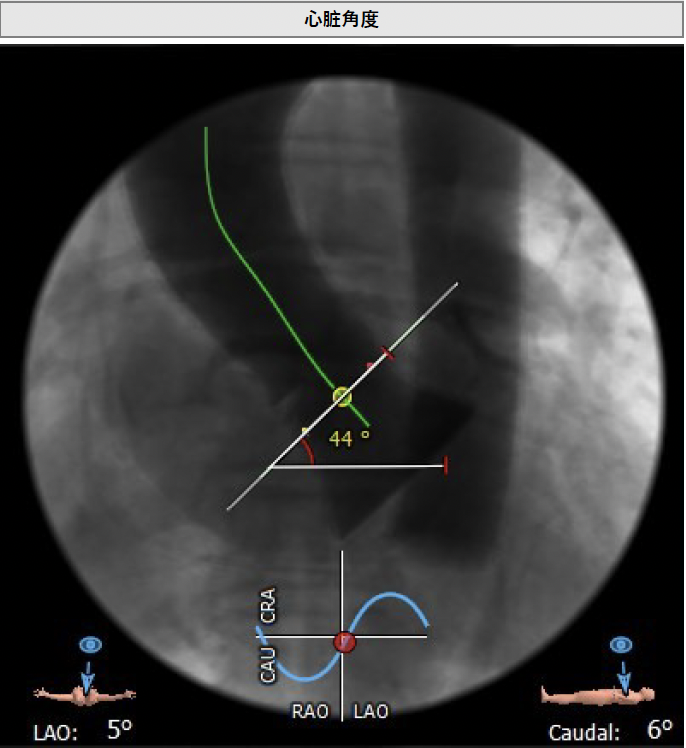

主动脉瓣角度 44°

升主动脉未见明显扩张,心脏角度:34°